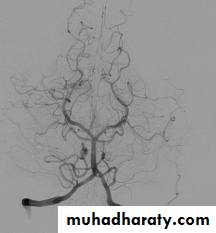

Cerebral angiography (the gold standard for evaluation of cerebral angiography) and can also demonstrate cerebral vasospasm

Angiographic vasospasm: asymptomatic arterial narrowing seen on angiography

Cerebral angiography